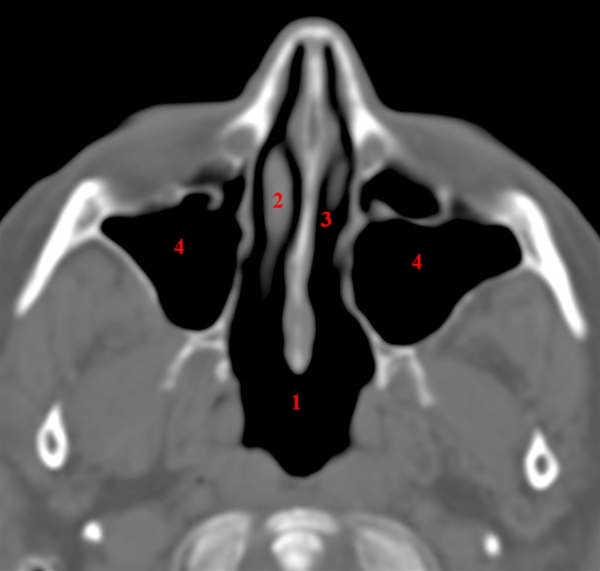

Maxillarsinus, axial, CT

CT-snit i axialplan (vandret plan) gennem normalt luftfyldte sinus maxillaris (kæbehuler).

1. Næsesvælget (nasopharynx eller rhinopharynx)

2. Næsemusling (concha nasalis)

3. Næsehule (cavum nasi)

4. Kæbehule (sinus maxillaris)